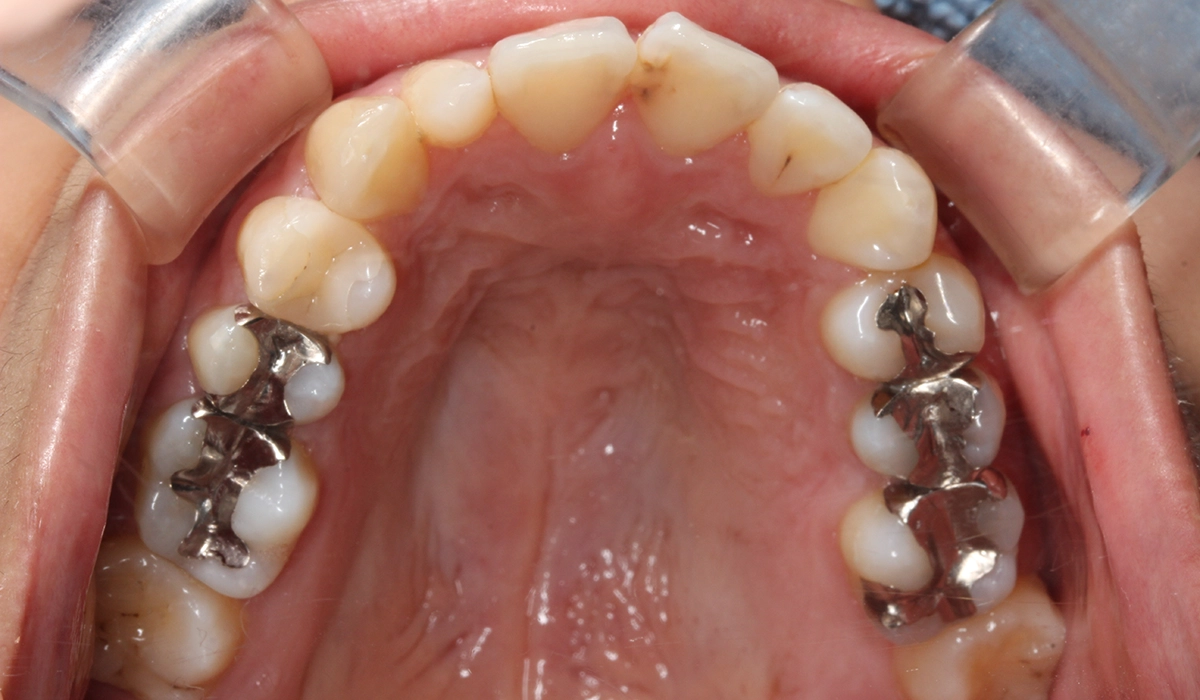

術前:下顎

術後:下顎

今回ご紹介する患者様は、上下の歯並びのガタツキを気にされており、矯正検査後叢生Ⅱ級と診断いたしました。

| 治療内容 | 上下の歯並びのガタツキを気にされており、矯正検査後叢生Ⅱ級と診断いたしました。 |